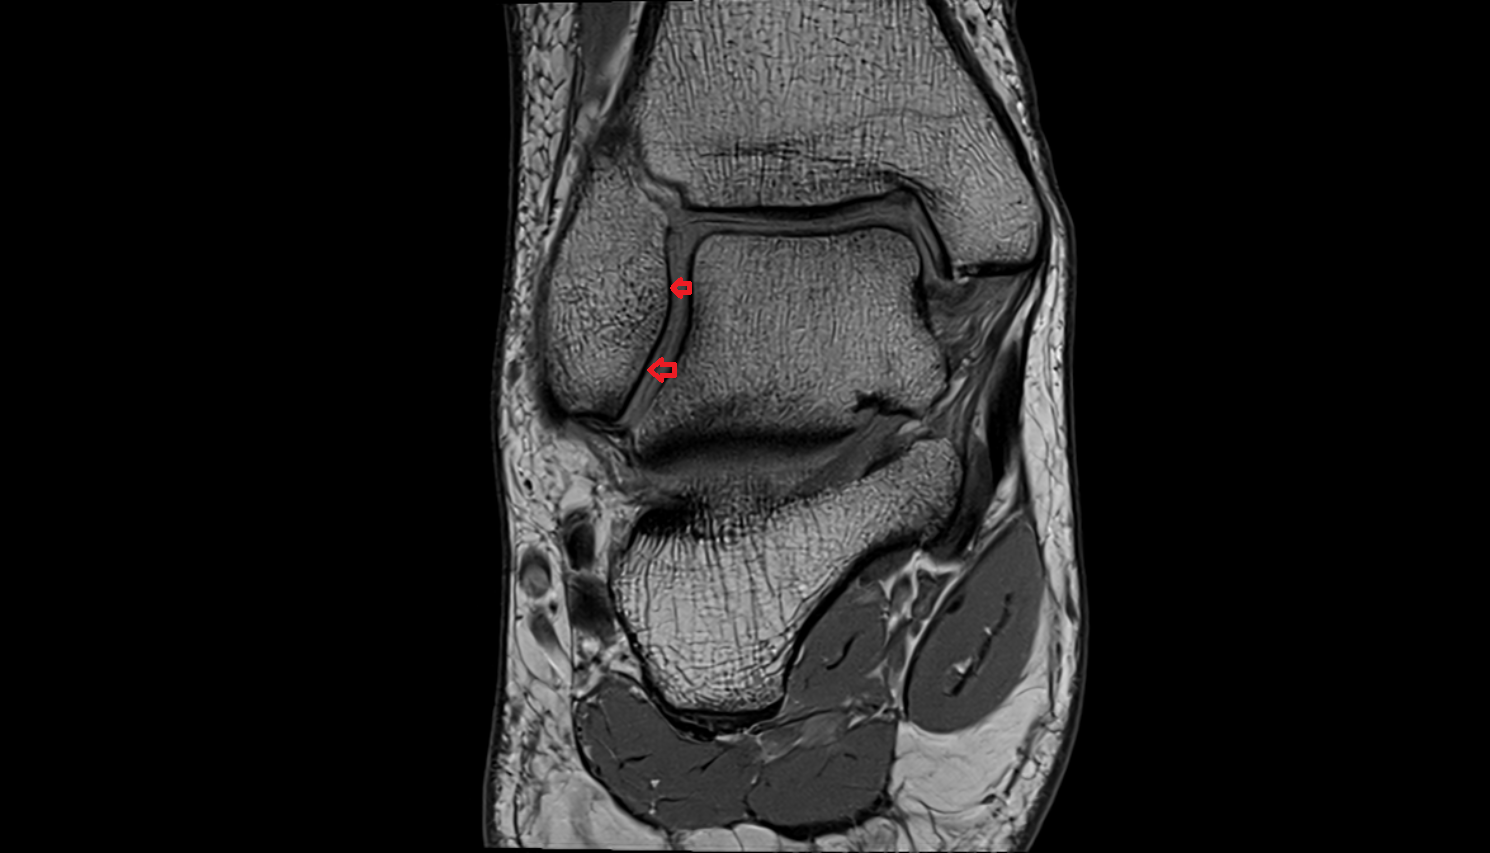

- Ankle joint

- Talus

- Body of talus

- Deltoid ligament complex

- Anterior talofibular ligament

- Posterior talofibular ligament